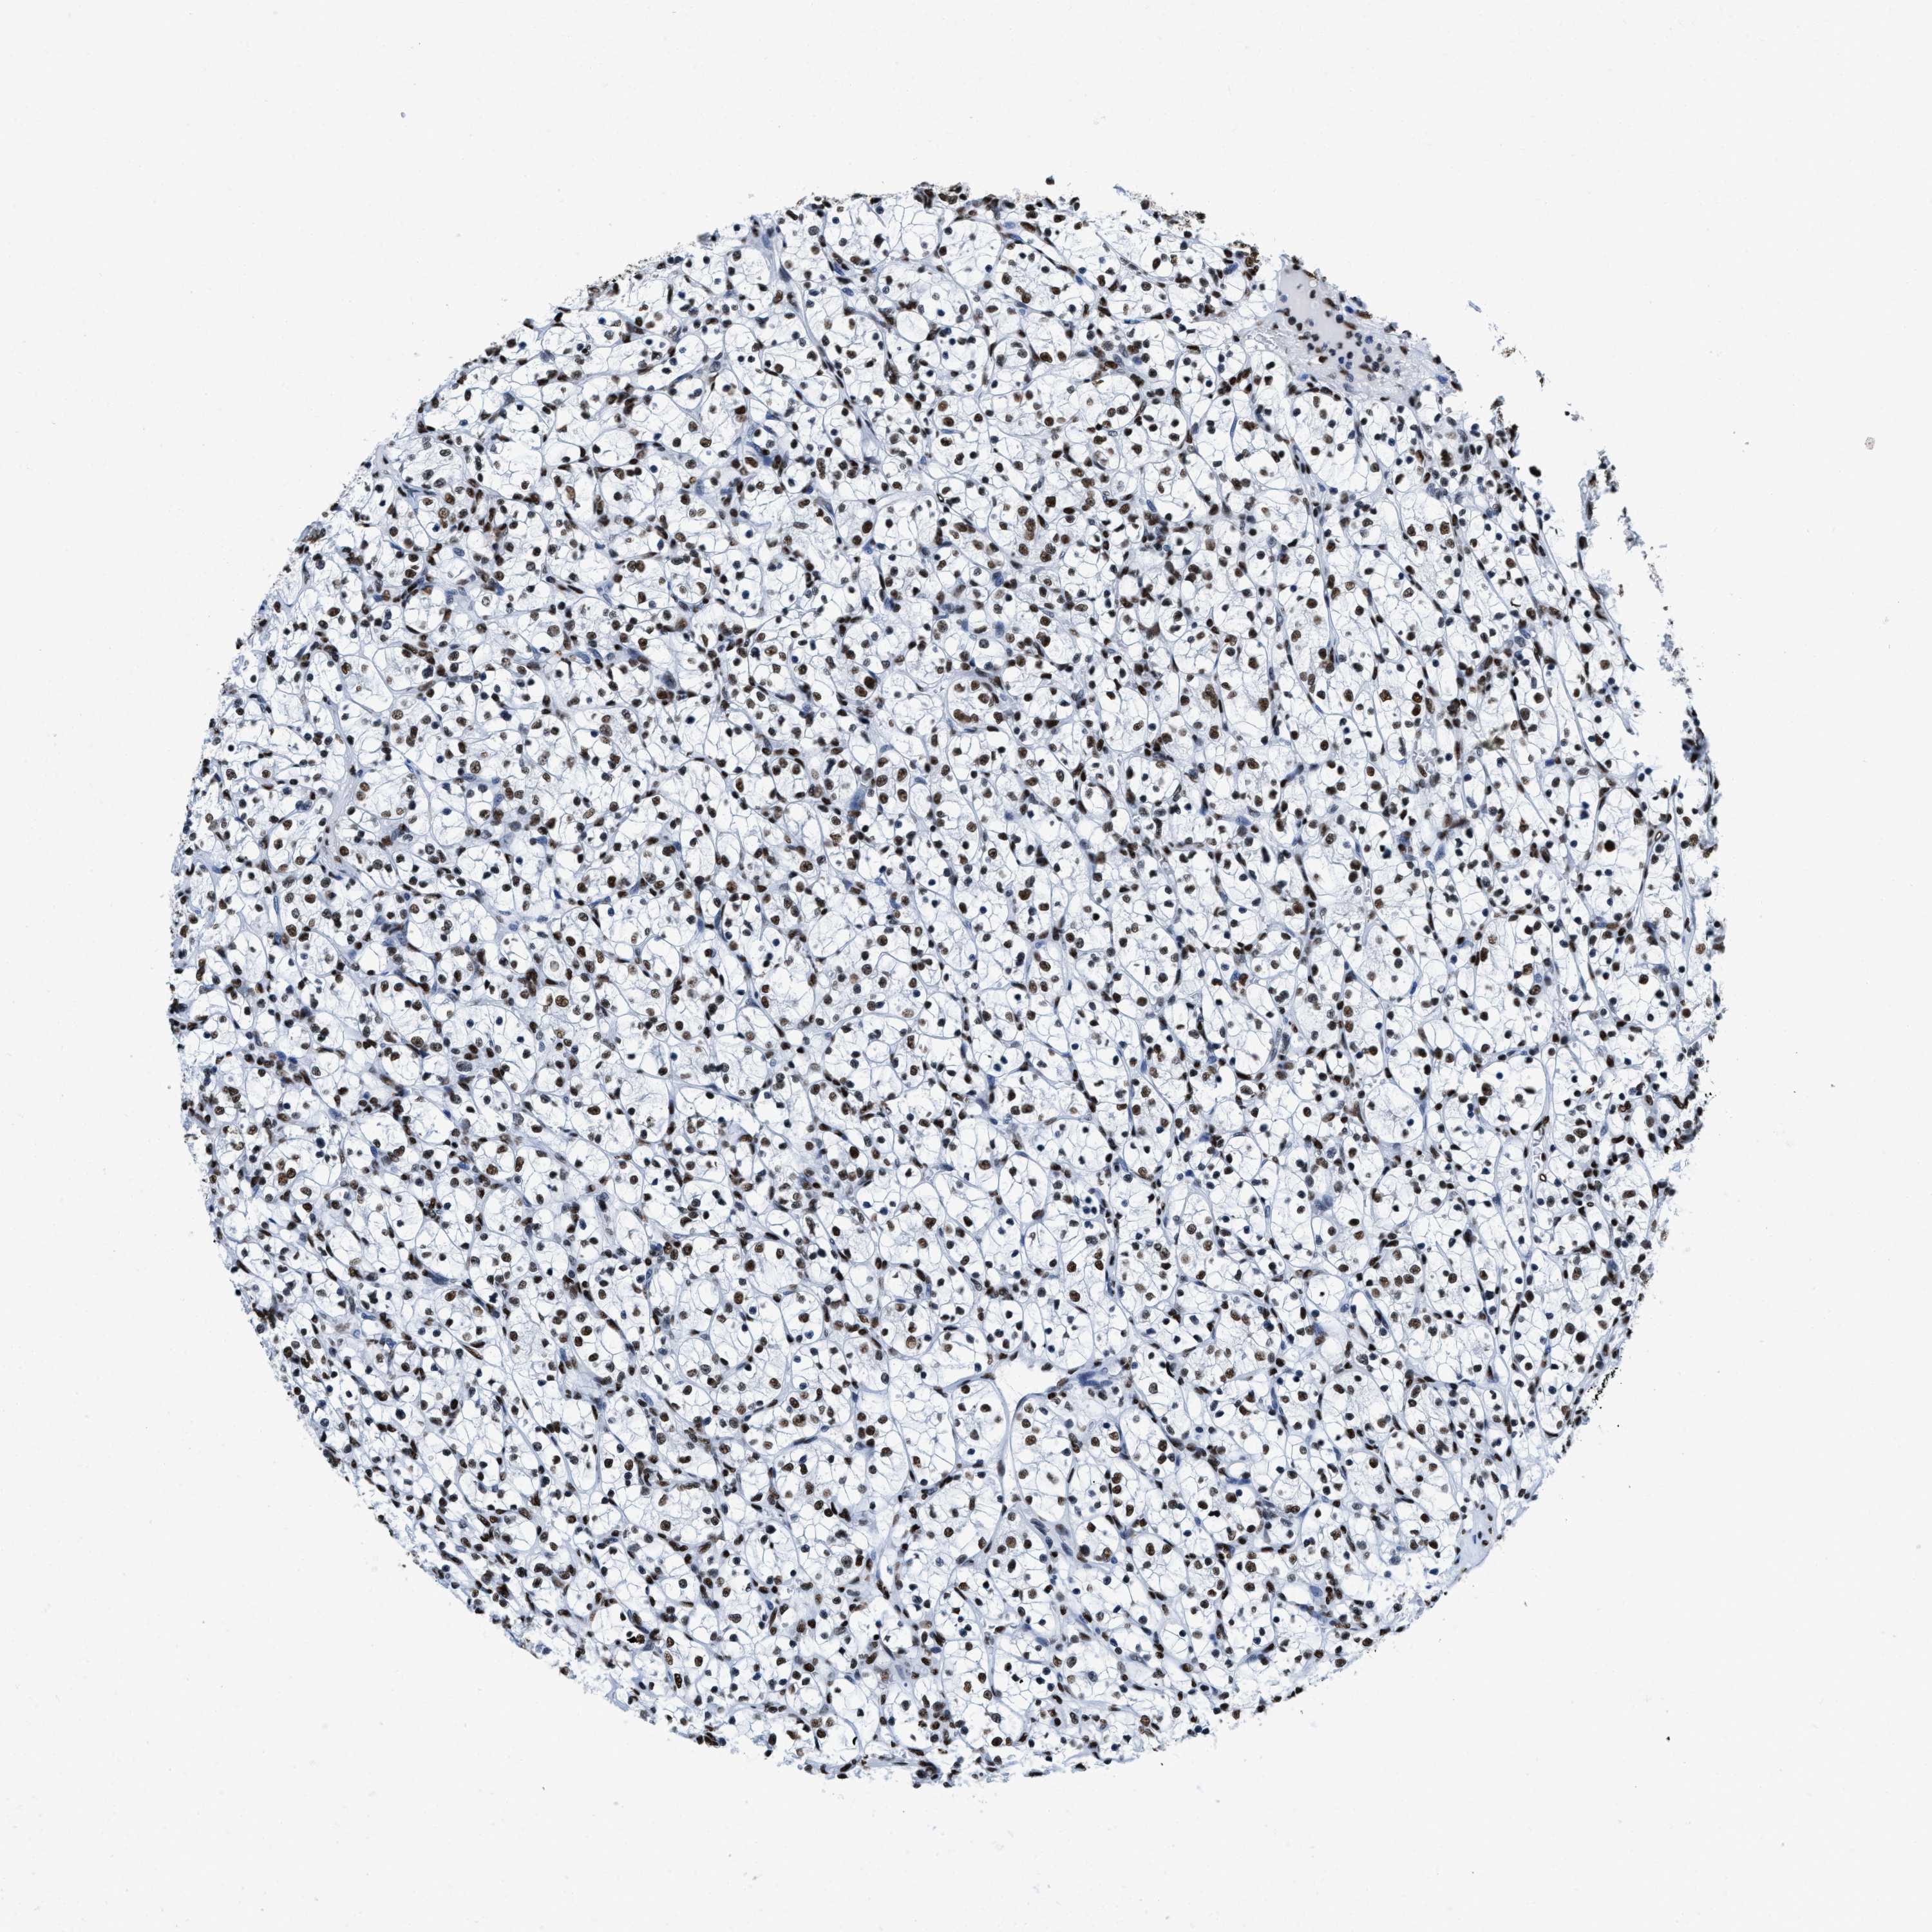

KIDNEY RENAL CLEAR CELL CARCINOMA (VALIDATION) - Interactive survival scatter ploti

The Survival Scatter plot shows the clinical status (i.e. dead or alive) for all individuals in the patient cohort, based on the same data that underlies the corresponding Kaplan-Meier plots. Patients that are alive at last time for follow-up are shown in blue and patients who have died during the study are shown in red.

The x-axis shows the expression levels (FPKM) of the investigated gene in the tumor tissue at the time of diagnosis. The y-axis shows the follow-up time after diagnosis (years). Both axes are complimented with kernel density curves demonstrating the data density over the axes. The top density plot shows the expression levels (FPKM) distribution among dead (red) and alive patients (blue). The right density plot shows the data density of the survived years of dead patients with high and low expression levels respectively, stratified using the cutoff indicated by the vertical dashed line through the Survival Scatter plot. This cutoff is automatically defined based on the FPKM cutoff that minimizes the p-score. The cutoff can be changed by dragging the vertical line or by entering a cutoff value in the square labeled "Current cut-off".

Under the Survival Scatter plot the p-score landscape (black curve; left axis) is shown together with dead median separation (red curve; right axis). Dead median separation is the difference in median mRNA expression between patients who have died with high and low expression, respectively. It is calculated as follows: median FPKM expression of dead patients with high expression - median FPKM expression of dead patients with low expression. This is intended to aid the user in visually exploring custom cutoffs and the associated p-scores and dead median separation.

Individual patient data is displayed and can be filtered by clicking on one or more of the category buttons on the top of the page. Categories describing expression level and patient information include: high, low, alive, dead, female, male and tumor stages. The scale of the x-axis can be toggled between linear and log-scale by clicking on the "x log" button. Mouse-over function shows TCGA ID, patient information and mRNA expression (FPKM) for each patient.

& Survival analysisi

Kaplan-Meier plots summarize results from analysis of correlation between mRNA expression level and patient survival. Patients were divided based on level of expression into one of the two groups "low" (under cut off) or "high" (over cut off). X-axis shows time for survival (years) and y-axis shows the probability of survival, where 1.0 corresponds to 100 percent.

SMARCC2 is not prognostic in Kidney Renal Clear Cell Carcinoma (validation)

Best expression cut offi

Based on the FPKM value of each gene, patients were classified into two groups and association between prognosis (survival) and gene expression (FPKM) was examined. The best expression cut-off refers the FPKM value that yields maximal difference with regard to survival between the two groups at the lowest log-rank P-value. Best expression cut-off was selected based on survival analysis .

When clicking on this number, the vertical dashed line indicating cut-off, the interactive survival plot, and the Kaplan-Meier curve will be adjusted to show results based on the best expression cut-off.

: 44.04

P scorei

Log-rank P value for Kaplan-Meier plot showing results from analysis of correlation between mRNA expression level and patient survival.

N/A

TCGA RNA samplesi

RNA-seq data is reported as average FPKM (number Fragments Per Kilobase of exon per Million reads), generated by the The Cancer Genome Atlas (TCGA) .

Normal distribution across the dataset is visualized with box plots, shown as median and 25th and 75th percentiles. Points are displayed as outliers if they are above or below 1.5 times the interquartile range. FPKM values of the individual samples are presented next to the box plot.

Average pTPM 43.8

Number of samples 100